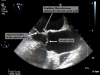

Cardiac papillary fibroelastoma is a rare, benign cardiac tumor. It often arises from valvular endocardium, and non-valvular endocardial location is rare. Although transthoracic echocardiography is usually sufficient for the diagnosis of most cardiac tumors, small tumors such as papillary fibroelastoma may be missed. Transesophageal echocardiography is superior to transthoracic echocardiography in diagnosing these tumors. Despite their benign histology, and independent of their size, they should be resected surgically because of their high potential for embolization. In this report, we present a case of papillary fibroelastoma located on the left atrial wall, presenting with symptoms of cerebral ischemia. The patient was treated surgically for the prevention of further embolic complications. Pertinent literature is also reviewed for this rare and benign cardiac tumor.